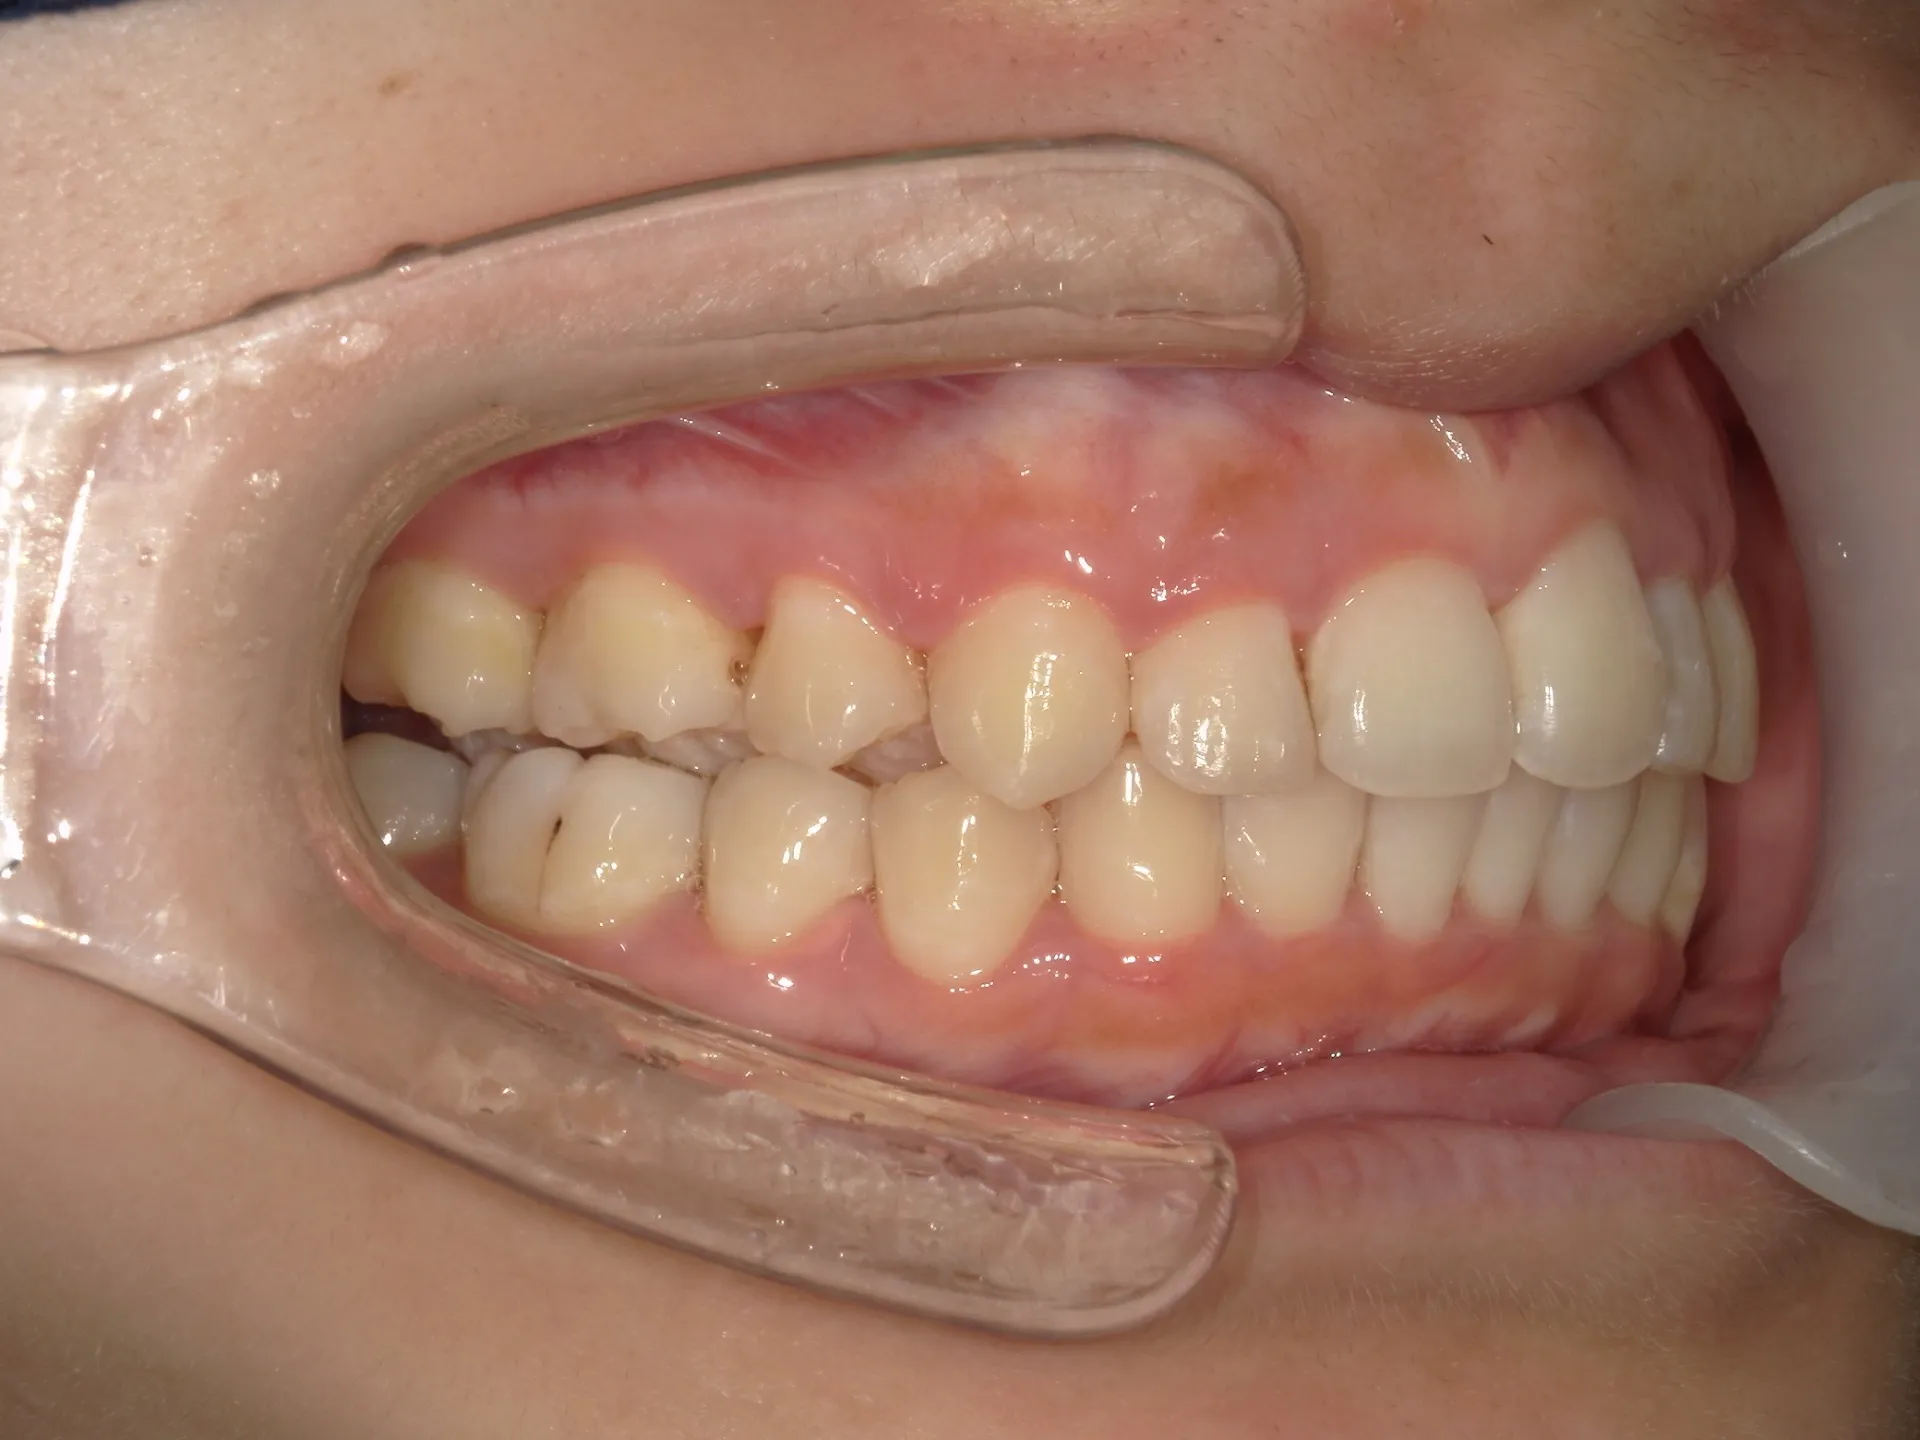

今回はマウスピース矯正(インビザライン)で前歯の出っ張りを治したケースをご紹介いたします。

マウスピース矯正で前歯の出っ歯感を抑えることが可能で、このケースでは上の歯のみ2本の抜歯を行っています。